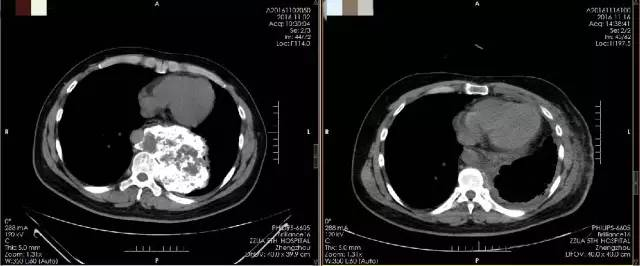

患者术前、后CT片